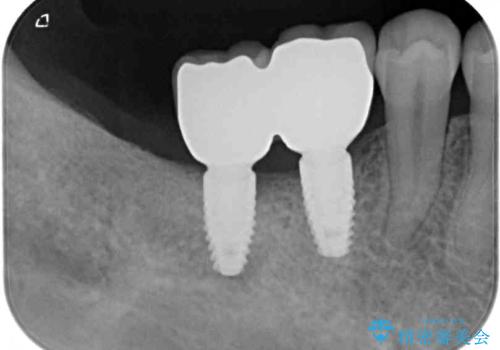

不正咬合で抜歯となった奥歯 インプラントによる咬合回復

歯周病により抜歯が必要と診断されたとのことでしたが、実際は奥歯以外に歯周病の所見はなく、不正な咬み合わせにより負担が過剰となり、歯を支える歯槽骨が吸収している状態でした。

歯の周りの炎症が顕著であったため、抜歯後炎症が治まるのを待ち、咬み合わせが改善できる位置にインプラントを埋入することとしました。

長年の咬合により、周囲の奥歯がすり減っているため、よりインプラントが長い期間安定するよう、睡眠時にはマウスピースを装着することを強く推奨しています。